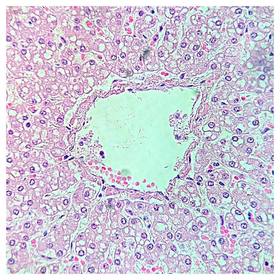

Láminas de Histología

Laboratorio de histología, Bibliografía Ross Pawlina 5ta Edición.